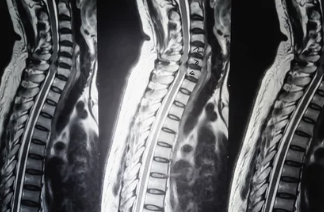

추간판 탈출증, 흔히 허리디스크라고 부르는 질환은

디스크가 신경을 눌러 허리통증, 다리저림, 보행장애까지 유발하는 대표적인 척추질환입니다.